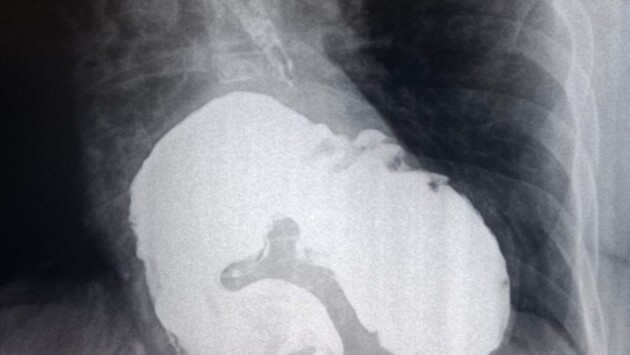

В ККБ №2 при проведении стандартного обследования, рентгеноскопии пищевода, желудка и двенадцатиперстной кишки, у пациентки была выявлена редкая патология.

У женщины, которая наблюдалась у кардиолога с жалобами на одышку и боли в сердце, обнаружили гигантскую грыжу пищеводного отверстия диафрагмы.